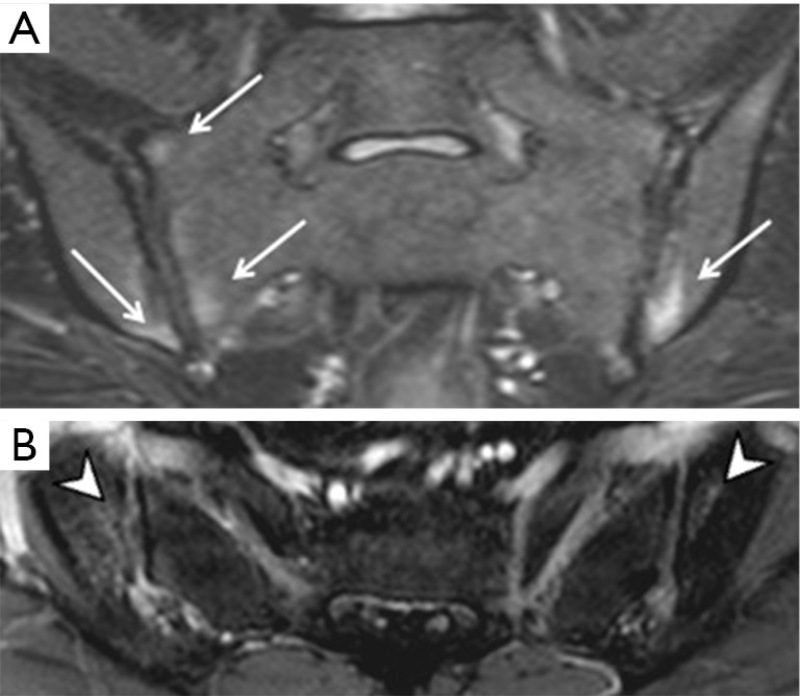

Hình ảnh chụp MRI viêm khớp cùng chậu

Hình ảnh Mri viêm khớp cùng chậu

Viêm khớp cùng chậu gây ra tình trạng dính khớp hoặc bắc cầu xương

Viêm khớp cùng chậu xuất hiện biến chứng

Viêm khớp cùng chậu đã biến chứng thành phù tủy xương, xói mòn hoàn toàn khớp cùng chậu